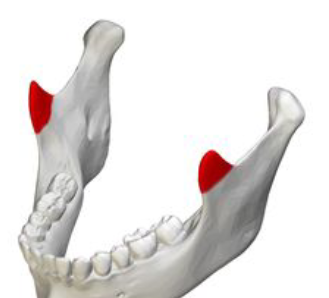

8

Q

what muscles attaches to the red bit

A

temporalis and masseter

How well did you know this?